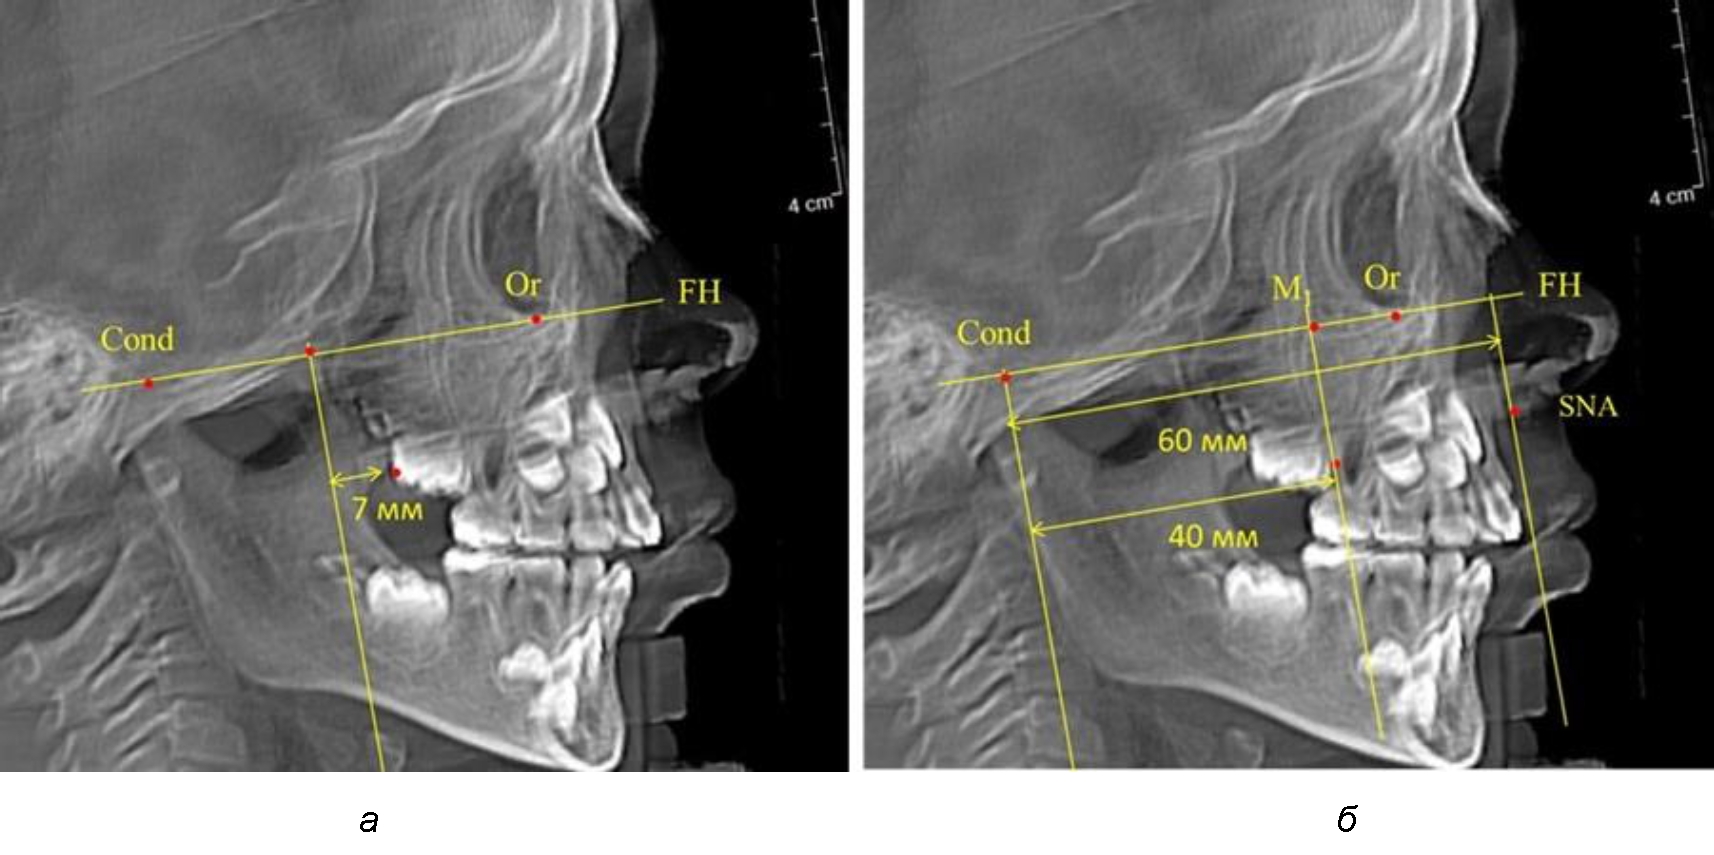

При проведении анализа к Франкфуртской горизонтали проводили передний и задний перпендикуляры. Передний спинальный перпендикуляр проходил через выступающую точку передней носовой ости (spina nasalis anterior – SNA), а задний суставной перпендикуляр опускали из кондилярной точки Cond. Молярный перпендикуляр проводили через медиальную поверхность первого постоянного моляра. Указанная вертикаль отделяла замещающие зубы постоянного прикуса от добавочных зубов (постоянных моляров), что вполне логично для анализа положения первых постоянных моляров в гнатическом комплексе (рис. 1).

Рис. 1. Метод определения положения первых верхних моляров по Ralph E. McDonald (а) и по предложенному методу (б)

Второй частью исследования был анализ положения первых постоянных моляров в различные периоды сменного прикуса. На телерентгенограммах детей периода прикуса молочных зубов дистальная поверхность зачатка первого постоянного моляра отстояла от крыловидной вертикали на величину, составляющую около 7 мм, что было близким по значению к данным R. E. McDonald. Сагиттальный размер гантического отдела составлял около 60 мм, а его отношение к кондилярно-молярной глубине – 1,5 (рис. 4).